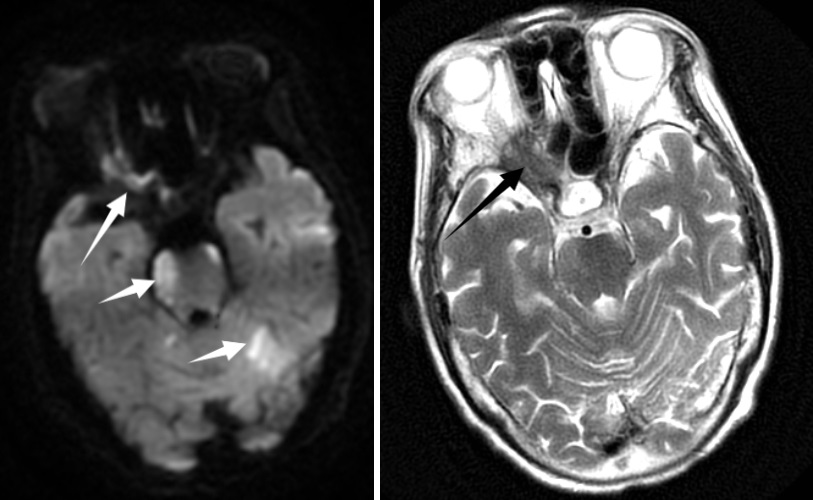

| 右侧眶尖见软组织团块,T1WI呈等/高信号,T2WI呈等/高信号,DWI呈等/高信号,ADC呈等/高信号,可见颅脑多发新鲜脑梗死 图 2 患者入院后头颅MRI |

患者,72岁女性,因“头痛伴反应差1 d,呕吐1次”入本院神经外科。患者入院前1 d突发头痛,伴意识状态差,不能行走,伴呕吐1次,呕吐物为胃内容物,无抽搐、发热。入院时体温36.5℃,血压187/97 mmHg(1 mmHg=0.133 kPa),神志嗜睡,表情淡漠,GCS评分12分,双侧瞳孔不等大,左侧直径2.5 mm,直接对光反射灵敏,间接对光反射消失,右侧直径4.0 mm,直接和间接对光反射均消失,双侧巴氏征阴性。既往曾出现右侧眼睑下垂,右眼视力变差,1个月前右眼视力丧失,曾在外院诊断为右侧视神经炎性假瘤,有高血压病史,否认手术史及免疫缺陷病史。入院头颅CT提示右侧视神经孔占位性病灶,视神经脑膜瘤可能(图 1)。头颅MR提示:①右侧基底节区、中脑、脑桥、双侧小脑半球多发斑点状/斑片状新鲜脑梗塞灶;②双侧基底节区、放射冠多发斑点状/斑片状脑梗塞灶或缺血变性灶;③右侧眶尖条片状异常信号灶,性质待定(图 2)。经神经内科会诊后考虑急性脑梗死,转入神经内科治疗,神经内科治疗上给予抗血小板、甘露醇脱水降颅内压、营养神经对症处理。患者入院后反复出现发热,发热原因未明,入院第2天经家属同意后行腰椎穿刺留取脑脊液行高通量基因测序。入院第3天,患者病情加重,神志转昏迷,复查头颅提示:①鞍上池、环池、天幕缘见片状稍高密度,考虑蛛网膜下腔出血。脑干、左侧小脑半球见斑片状低密度灶,范围大致如前,考虑脑梗塞,脑干片状低密度灶密度更低,请结合临床;②脑白质病变,脑萎缩,同前;③右侧眶尖部见片状软组织密度影,大小约16 mm×9 mm,性质待定,同前片,建议MR平扫+增强检查协诊(图 3)。考虑蛛网膜下腔出血合并脑室系统扩张,转神经外科急诊行脑室外引流+全脑血管造影术,脑血管造影未见脑动脉瘤及畸形改变(图 4)。术后转入ICU监护治疗,转入ICU后脱水降颅内压、抗感染、脑保护、预防脑血管痉挛等治疗。患者术后出现双侧瞳孔散大,复查头颅提示蛛网膜下腔出血较前增多,双脑室积血、积气,脑干、左侧小脑半球见斑片状低密度灶。入院第4天,脑脊液高通量基因检测结果报告为烟曲霉感染,脑脊液及血液半乳甘露聚糖检测(GM试验,金域)结果分别为6.19/1.42,阳性。综合病史、CT及MR结果,临床诊断为脑烟曲霉感染,改用伏立康唑注射液积极抗真菌治疗,白蛋白联合激素脱水减轻脑水肿、尼莫地平抗脑血管痉挛及脑保护等综合措施。患者体温热峰下降,但持续深昏迷,神经反应差,入院第7天家属放弃治疗出院。

脑曲霉菌感染合并蛛网膜下腔出血较为少见,文献报道多为个案[8]。本例患者肺部及鼻窦部菌未发现曲霉菌感染临床表现以及影像学表现,但头颅CT可见右侧蝶窦外侧骨质缺失,临近眶尖见软组织团块,软组织团块与视神经、眼肌分界不清。MRI见右侧眶尖见软组织团块,T1WI呈等/高信号,T2WI呈等/高信号,DWI呈等/高信号,ADC呈等/高信号,行脑血管造影时未见眼眶有造影剂聚集,结合患者入院2月前在外院发现右侧视神经孔占位性病变并行激素冲击治疗,因而,临床高度考虑患者右侧视神经孔曲霉菌感染,经激素冲击治疗后此位置的直接蔓延导致颅内曲霉菌感染。遗憾的是,入院后患者病情变化迅速,未能获取右侧视神经孔活检进一步明确诊断。尽管在入院第4天明确脑曲霉菌感染,并给予伏立康唑注射液积极抗真菌治疗,但患者病情进展迅猛未能获得良好预后。本例患者急性多发脑梗死及蛛网膜下腔出血考虑与烟曲霉侵犯嗜血管性有关,颅内组织缺血缺氧性坏死,造成脑血管意外的发生,而曲霉菌引起的变态反应加重或导致了恶性脑水肿,最终造成患者不良预后。